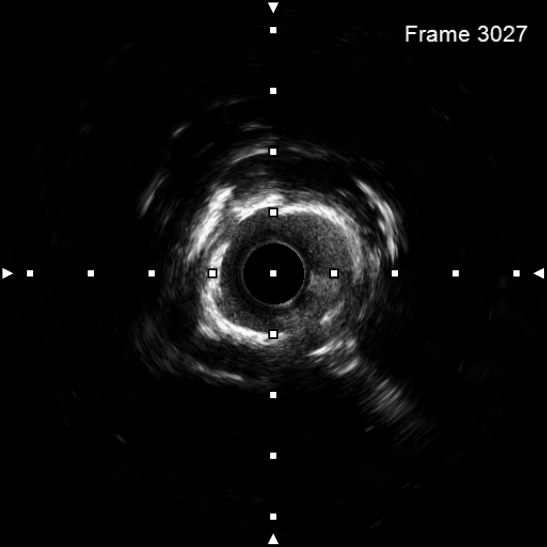

图4 3.0 Shockwave处理后可见钙化断裂 高压球囊验证膨胀良好

该患者入院后,完善相关检查并再次建议行CABG治疗,但家属仍拒绝,遂考虑再次行PCI手术干预。冠脉造影提示患者冠脉右冠状动脉中段70-95%再狭窄,左主干末端80%狭窄,前降支原支架中远段 80-95%再狭窄,回旋支完全闭塞,急需手术尽快解决冠脉血流灌注问题,否则随时有生命风险,但患者多处支架内/节段内再狭窄,造影提示钙化明显,外院已尝试无法扩张,经手术团队充分讨论后,计划在IABP支持下,先进行右冠状动脉干预,利用IVUS精准评估原支架再狭窄部位情况,采用旋磨或Shockwave冲击波球囊处理无法扩张的病变部位,右冠处理后择期进行左冠状动脉干预。在制定了详尽的手术计划后,手术团队首先对患者的右冠状动脉行IVUS检查,结果提示该患者右冠中段支架局部膨胀不良,局部支架面积6.67mm²,管腔内多处可见钙化小结及270°以上钙化,IVUS钙化积分达3分。由于膨胀不良处原支架后方可见钙化斑块,常规旋磨效果不佳,对于此类钙化病变,IVL处理是最佳方案。手术团队对近端采取棘突球囊及高压球囊进行扩张,采用Guidezilla辅助下输送3.0mmx12mm Shockwave冲击波球囊于右冠钙化处进行冲击波钙化斑块碎裂术,通过IVUS证实支架内的新生钙化病变得到松解,原膨胀不良部位支架面积达到7.76mm²,后经过高压球囊充分预处理,顺利完成右冠支架植入,术后复查右冠原膨胀不良部位支架面积9.17mm²。

2天后再次干预患者左冠状动脉,首先开通回旋支并进行球囊扩张,采用IVUS进行前降支至左主干支架评估,IVUS提示左主干末端原支架内可见新生环状钙化病变,采用3.0x12mm Shockwave预处理后可见钙化断裂,并再次经高压球囊预处理,于前降支至左主干植入支架,术后造影及IVUS均提示支架膨胀良好,左主干MSA 9.96mm²。患者经介入干预后,胸痛症状较前明显缓解,体力活动较前恢复。